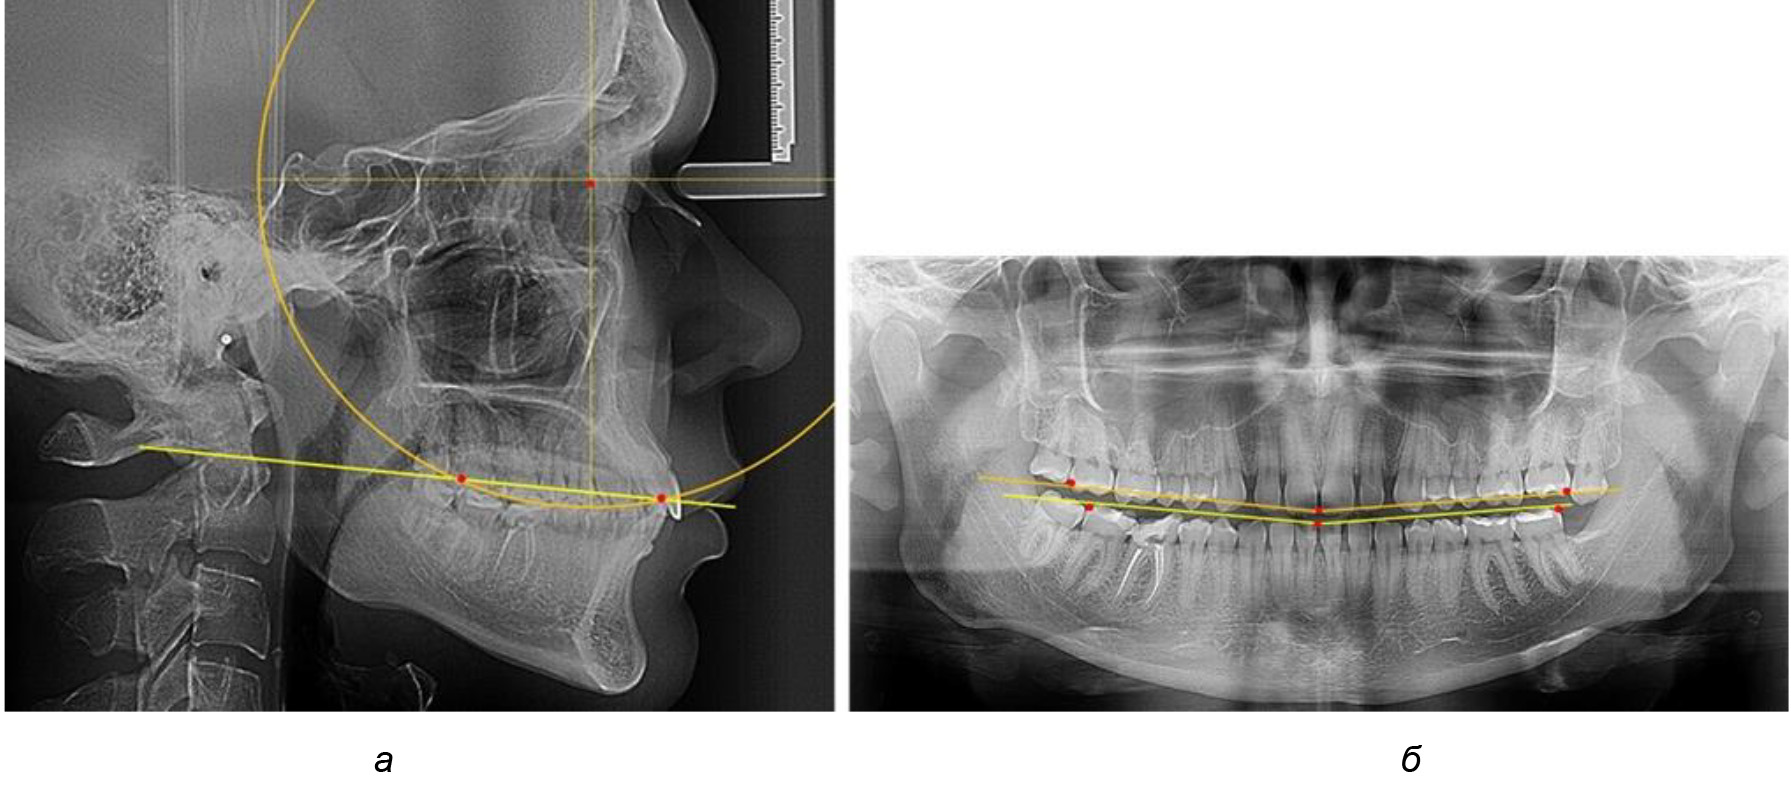

На рентгенограммах людей 2-й подгруппы (30 человек с нейтральным типом роста) величина угла нижней челюсти в среднем составила (120,34 ± 2,19) ° и характеризовала нейтральный тип нижней челюсти.

Глубина кривой Spee в среднем по 2-й подгруппе составил (3,54 ± 0,58) мм, что было незначительно меньше, чем при анализе аналогичного показателя 1-й подгруппы.

Достоверных различий с показателями, полученными при анализе ТРГ и ОПТГ, нами не отмечено (р ˃ 0,05). Деление величины радиуса круга к длине окклюзионной линии составило 1,612 ± 0,02, что, так же как и в 1-й подгруппе, было близким по значению к числу Фибоначчи (1, 618).

Рис. 3. Особенности кривой Spee на ТРГ (а) и ОПТГ (б) при нейтральном типе роста нижней челюсти